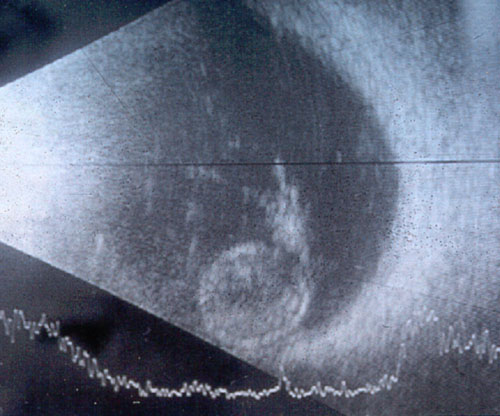

Figure 1.

B scan ultrasound of the proband's (II:1) right eye demonstrating complete lens dislocation into the vitreous cavity. All eight affected individuals in this pedigree similarly demonstrated complete lens dislocation.